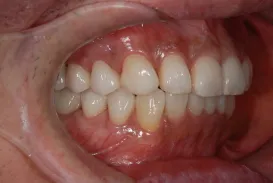

初診時

| 患者様のお悩み | 外傷で歯が抜けた |

|---|---|

| 治療法・使用素材 | インプラント治療の後、セラミック治療 |

| 患者様の年代 | 20代 |

| 治療開始年齢 | 20代 |

| 治療にかかった期間 | 8か月 |

| 性別 | 女性 |

| この治療のリスクについて | インプラントが正しい位置に入るかどうか |

| 治療にかかった費用 | 45万円 |